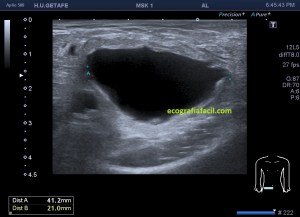

En el caso que te traigo hoy no hizo falta buscar mucho, nada más poner la zona en corte transverso en la región inguinal derecha, cerca de los labios mayores, la paciente tenía una masa blanda, ligeramente dolorosa durante la exploración que había aumentado ligeramente tiempo atrás y que ecográficamente tenía un aspecto anecoico,imagen 1, de paredes finas, más grande en su eje lateral que en el eje antero posterior y que se deformaba con la ligera presión del transductor y que no modificaba su ecoestructura con la maniobra de Valsalva.

En cuanto localicé este hallazgo realicé corte transverso (imagen 2) y longitudinal (imagen 1), con medidas y estudio en modo doppler para ver vascularización (imagen 3, flecha amarilla), seguidamente, era muy importante asegurar algunas referencias locoregionales como los grandes vasos femorales, siempre debemos documentar esta coexistencia y buscar un cuello que puedes observar con las dos flechas rojas de la imagen 1 y que la ecoestructura marca perfectamente al ser anecoica.

Aunque no muchas, ya había visto alguna vez esta entidad y sabía que era un Quiste de Nuck, pero necesitaba buscar los hallazgos anatómico ecográficos previamente comentados, como la localización junto a los grandes vasos y el cuello, para poder presentarlo a la radióloga para que realizase el informe, que corroboró lo que pensaba, lo cual no tiene relevancia alguna. Esta patología puede ser conocida también como Hidrocele de Nuck.

1

2

3